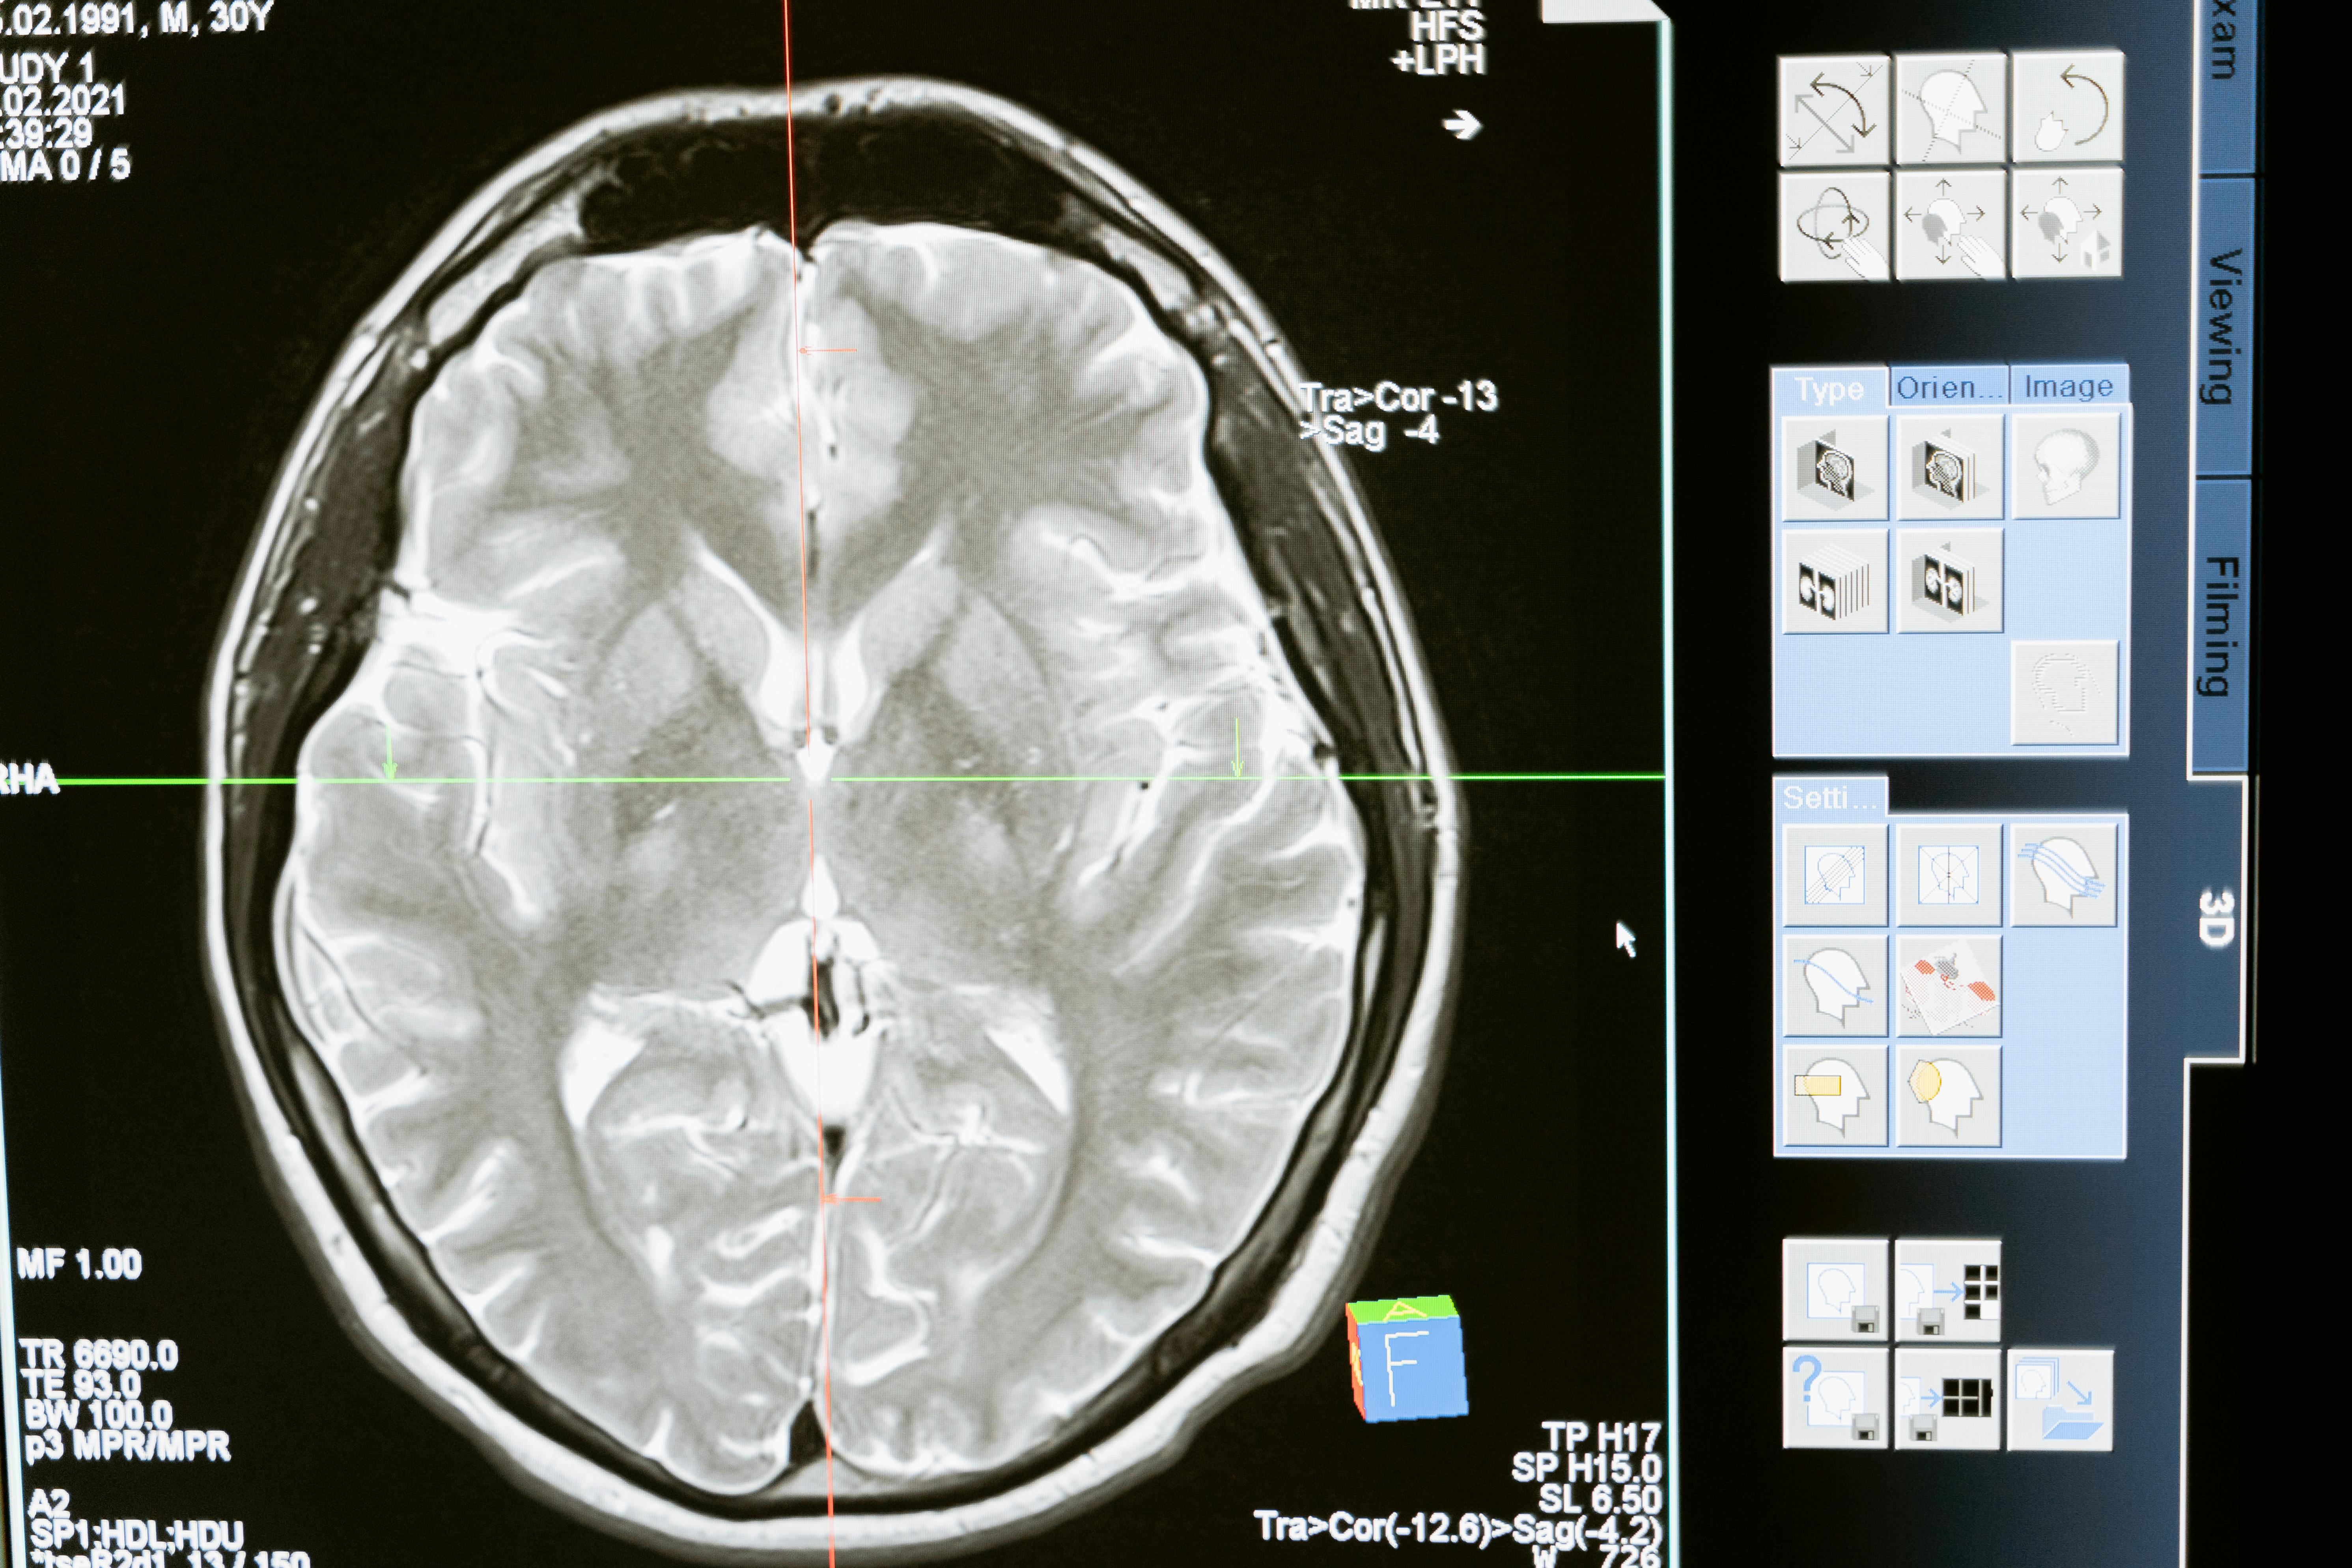

- Interpretação de imagens cerebrais : os neurologistas devem saber ler e interpretar as ressonâncias magnéticas, as ecografias, as angiografias e outras técnicas de imagiologia. Por exemplo, devem ser capazes de identificar anomalias estruturais, lesões, tumores ou sinais de doença degenerativa.